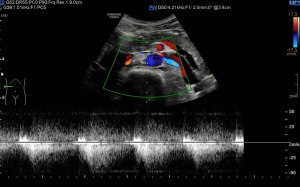

Los vientres anteriores de los músculos Digástricos, que son el objeto del desarrollo de este Post, son dos estructuras musculares redondeadas en el corte transversal, imagen 1, y alargados si los estudiamos en el eje largo, imagen 3, mira:

Ecográficamente los músculos digástricos en eje corto tienen semiología hipoecogénica, en aspecto de noche estrellada, como la de hoy, y en el eje largo en forma de penacho o en forma de plumas con las fibras alargadas y paralelas a la superficie.

Acostúmbrate a mirar esta anatomía en los estudios de cuello sobre todo en pacientes infantiles, por posible localización de adenopatías. En la edad adulta pueden objetivarse cambios de grosor, infrecuentemente, en esta musculatura por diferentes motivos.